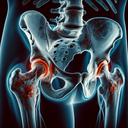

МРТ кульшових суглобів

Магнітно-резонансна томографія (МРТ) кульшових суглобів є неінвазивним методом діагностики, що використовує магнітне поле та радіохвилі для отримання детальних зображень внутрішніх структур. ### Переваги МРТ: - **Висока роздільна здатність:** Дає змогу отримати чіткі зображення, що допомагає виявити пошкодження м'язів, сухожиль і зв'язок. - **Безпека:** Не використовує іонізуюче випромінювання, що робить його безпечним для пацієнтів...